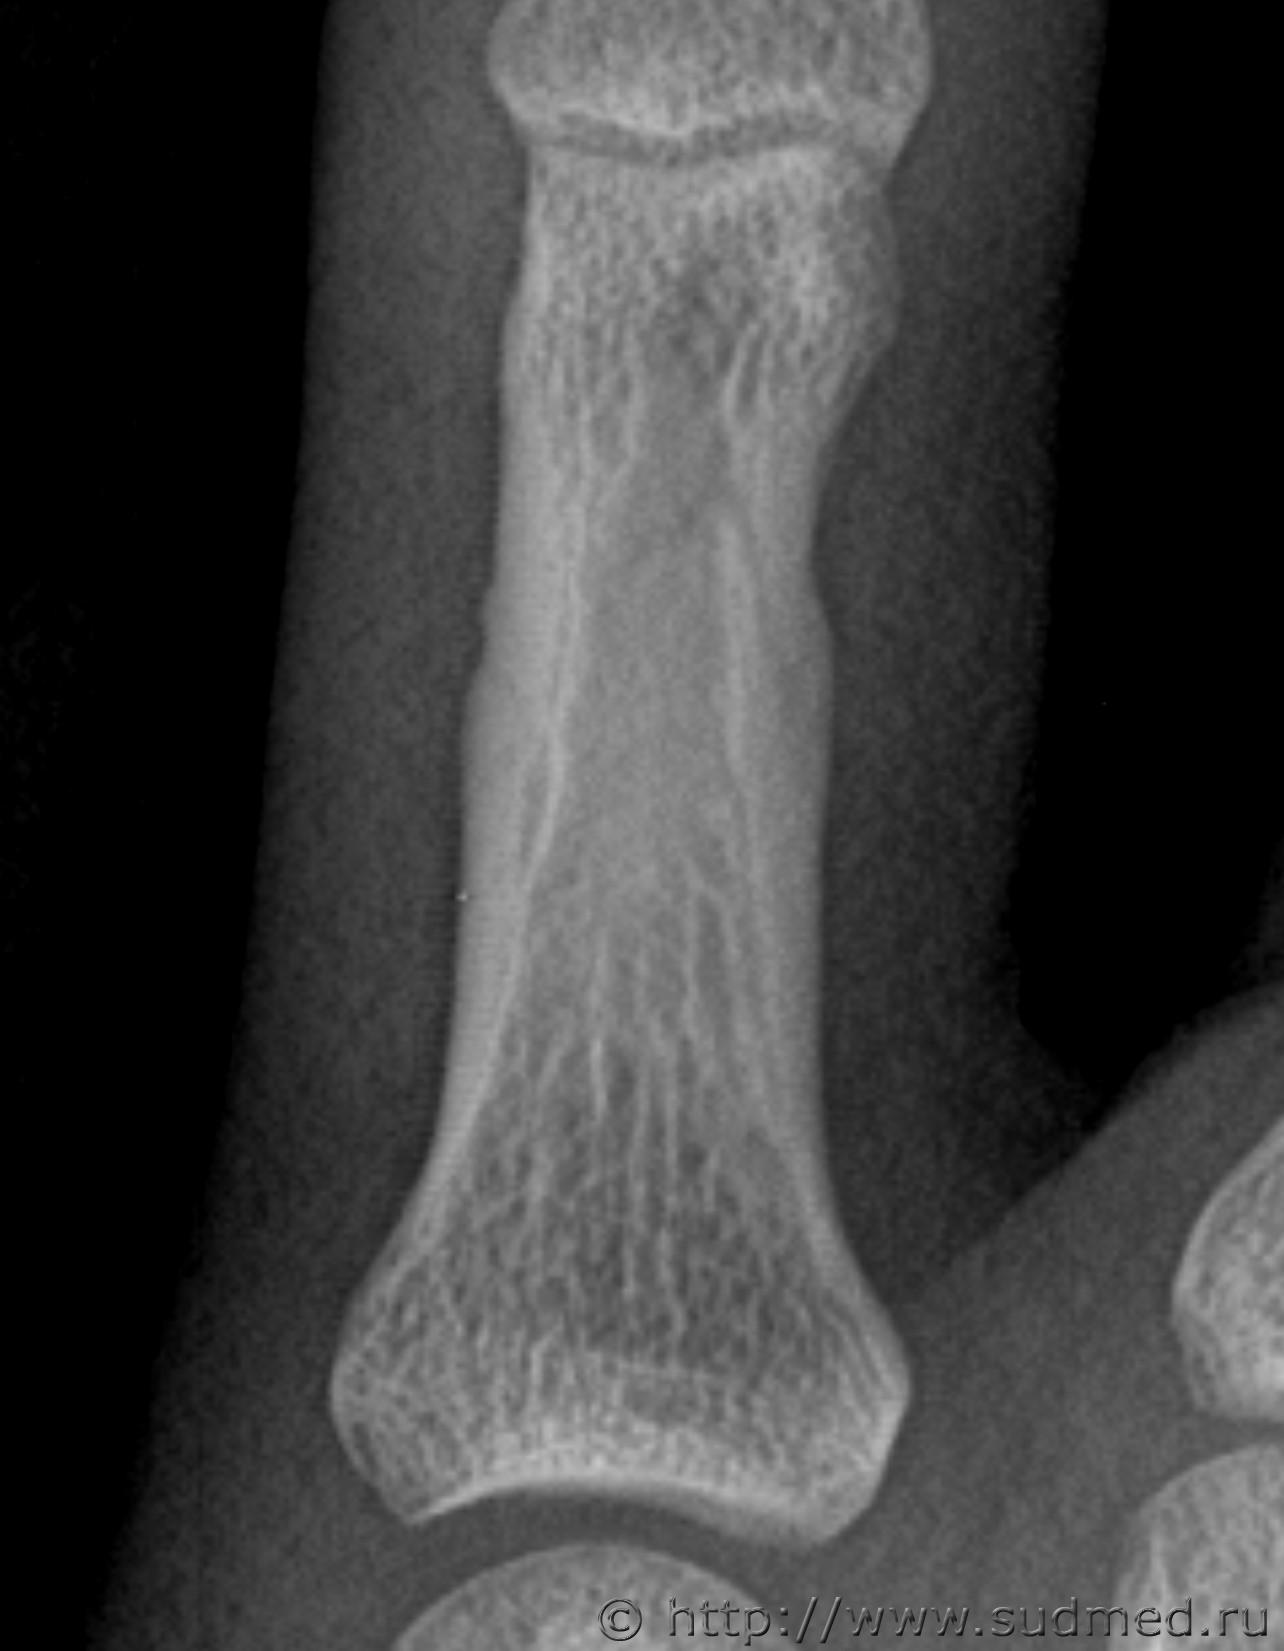

Здравствуйте. Произошла драка в которой когда я упал и меня пинали по голове, я закрыл голову рукой и нападавший попал ногой по руке. В результате он повредил мне мизинец на левой руке. Врач скорой сказала что это скорее всего ушиб. Я думал что ушиб пройдет, но палец болел и через 13 дней я обратился в травмпункт, мне сделали рентген кисти и обнаружили «З/консолидирующийся перелом о/фаланги Vп левой кисти». По этой справке мне определили средний вред здоровью. Потом когда суд мед эксперты смотрели данный снимок они не нашли перелома. Снимок сделан в травм пункте на 13 день после травмы. Можете ли вы оценить снимки. Что на них видно? Какая степень вреда здоровью?

Скорее всего технический сбой. Вот изображения в другом формате.

В справке из травм пункта на 13 день после травмы указано:

Установлен диагноз: З/консолидирущийся перелом о/фаланги Vп левой кисти.

По поводу первого снимка, 13 дней после травмы. На диске, цифровой.

Заключение: на представленных рентгенограммах 5 пальца левой кисти от (13 дней после травмы) на электронном носителе костно-травматических изменений не выявляется.

Снимки цифровые 13 дней после травмы: